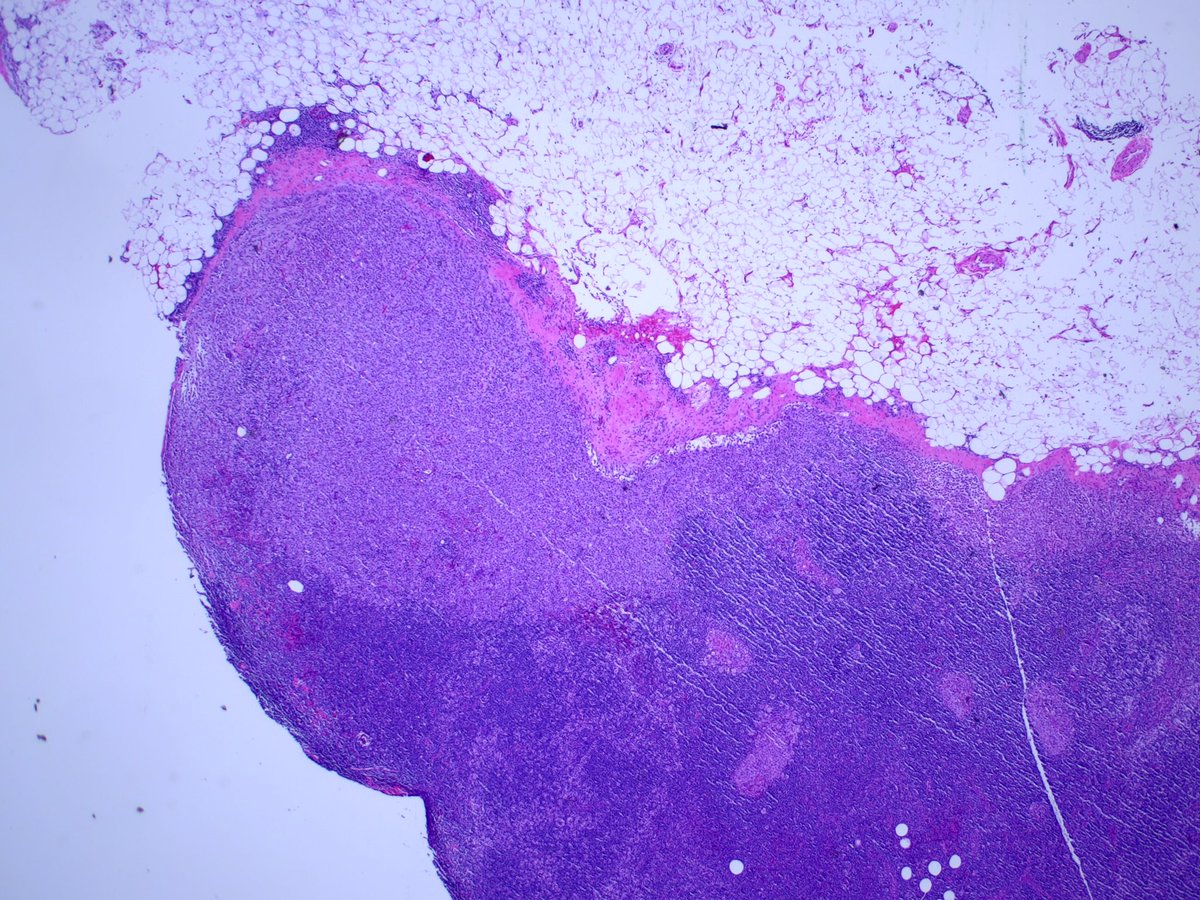

52 Year old female; multifocal right sided breast cancer undergoing mastectomy with SLN bx.

Intraoperative sentinel node touch prep shown. If cancer —> axillary dissection.